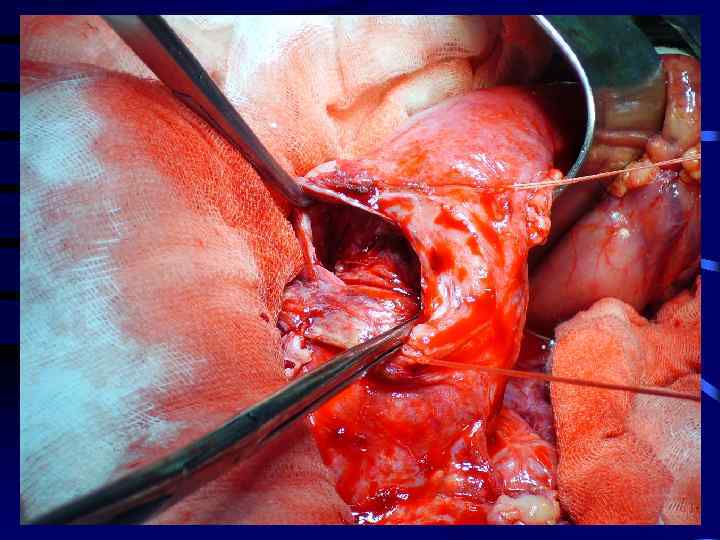

Кисты ложные хвоста поджелудочной железы

Виды дренирования кист